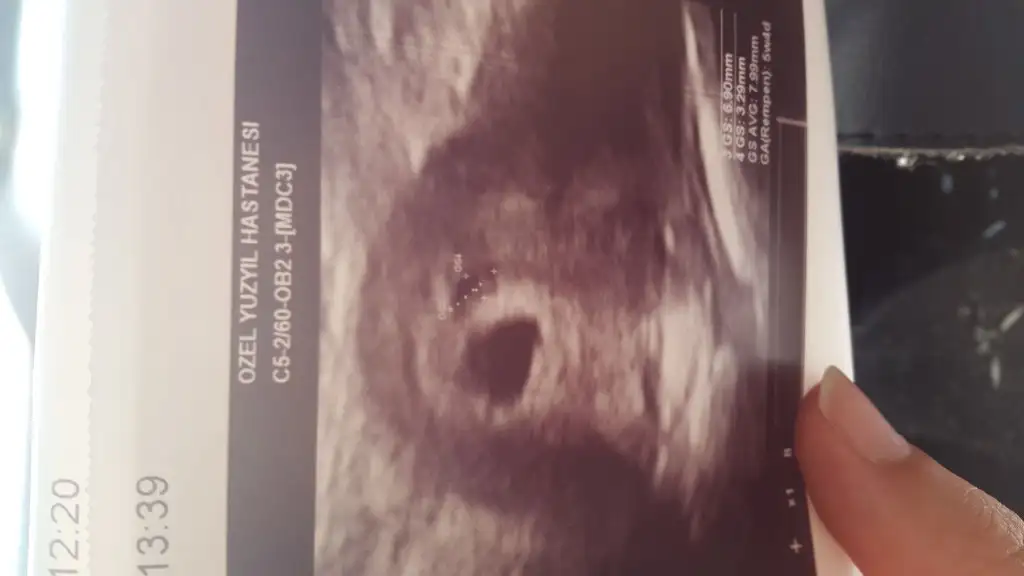

Canım cok gecmıs olsun inanmıyorum ya kadına bak okurken sinir oldum yat dinlet canım ve üzüm olayına da cok şaşırdım hıc bilmiyordum baska Zararlı bıseyler saydımı pekiKizlar doktora gittim ben dusuk riskim varmis yememem gereken seyleri saydi ve uzum dedi sok oldum dun aksam koca bi salkim uzum yedim hic bilmiyodum dusuk yapuomus sakin yemeyin igne ve fitil verdi bakalim kesemin gelisimi normalmis bi onceki olcume gore resmi yukledim yuvarlak yer kesem isaretledigi yerde kanama bolgesiymis bide kanama olunca mutlaka gidin bence doktora doktorumu degistircem bende bayandi gercekten erkek doktorlar daha cok ilgileniyomus inanmiyodum basima geldi .... bana telefondan dogru normal bekle dio beklesem belki dusucekti neye gore verio acaba bu karari ...

Geçmiş olsun kardeşKizlar doktora gittim ben dusuk riskim varmis yememem gereken seyleri saydi ve uzum dedi sok oldum dun aksam koca bi salkim uzum yedim hic bilmiyodum dusuk yapuomus sakin yemeyin igne ve fitil verdi bakalim kesemin gelisimi normalmis bi onceki olcume gore resmi yukledim yuvarlak yer kesem isaretledigi yerde kanama bolgesiymis bide kanama olunca mutlaka gidin bence doktora doktorumu degistircem bende bayandi gercekten erkek doktorlar daha cok ilgileniyomus inanmiyodum basima geldi .... bana telefondan dogru normal bekle dio beklesem belki dusucekti neye gore verio acaba bu karari ...

Canım çok geçmiş olsun wc dışında ayağa kalkma.. Rabbim bebeklerimizi korusun.. benim doktorum da üzüm çok yeme, fazla şeker var demişti ama düşük yaptırıyor demedi ilginç gerçektenKizlar doktora gittim ben dusuk riskim varmis yememem gereken seyleri saydi ve uzum dedi sok oldum dun aksam koca bi salkim uzum yedim hic bilmiyodum dusuk yapuomus sakin yemeyin igne ve fitil verdi bakalim kesemin gelisimi normalmis bi onceki olcume gore resmi yukledim yuvarlak yer kesem isaretledigi yerde kanama bolgesiymis bide kanama olunca mutlaka gidin bence doktora doktorumu degistircem bende bayandi gercekten erkek doktorlar daha cok ilgileniyomus inanmiyodum basima geldi .... bana telefondan dogru normal bekle dio beklesem belki dusucekti neye gore verio acaba bu karari ...

canım çok geçmiş olsun inşallah risk ortadan kalkar en kısa zamandaKizlar doktora gittim ben dusuk riskim varmis yememem gereken seyleri saydi ve uzum dedi sok oldum dun aksam koca bi salkim uzum yedim hic bilmiyodum dusuk yapuomus sakin yemeyin igne ve fitil verdi bakalim kesemin gelisimi normalmis bi onceki olcume gore resmi yukledim yuvarlak yer kesem isaretledigi yerde kanama bolgesiymis bide kanama olunca mutlaka gidin bence doktora doktorumu degistircem bende bayandi gercekten erkek doktorlar daha cok ilgileniyomus inanmiyodum basima geldi .... bana telefondan dogru normal bekle dio beklesem belki dusucekti neye gore verio acaba bu karari ...